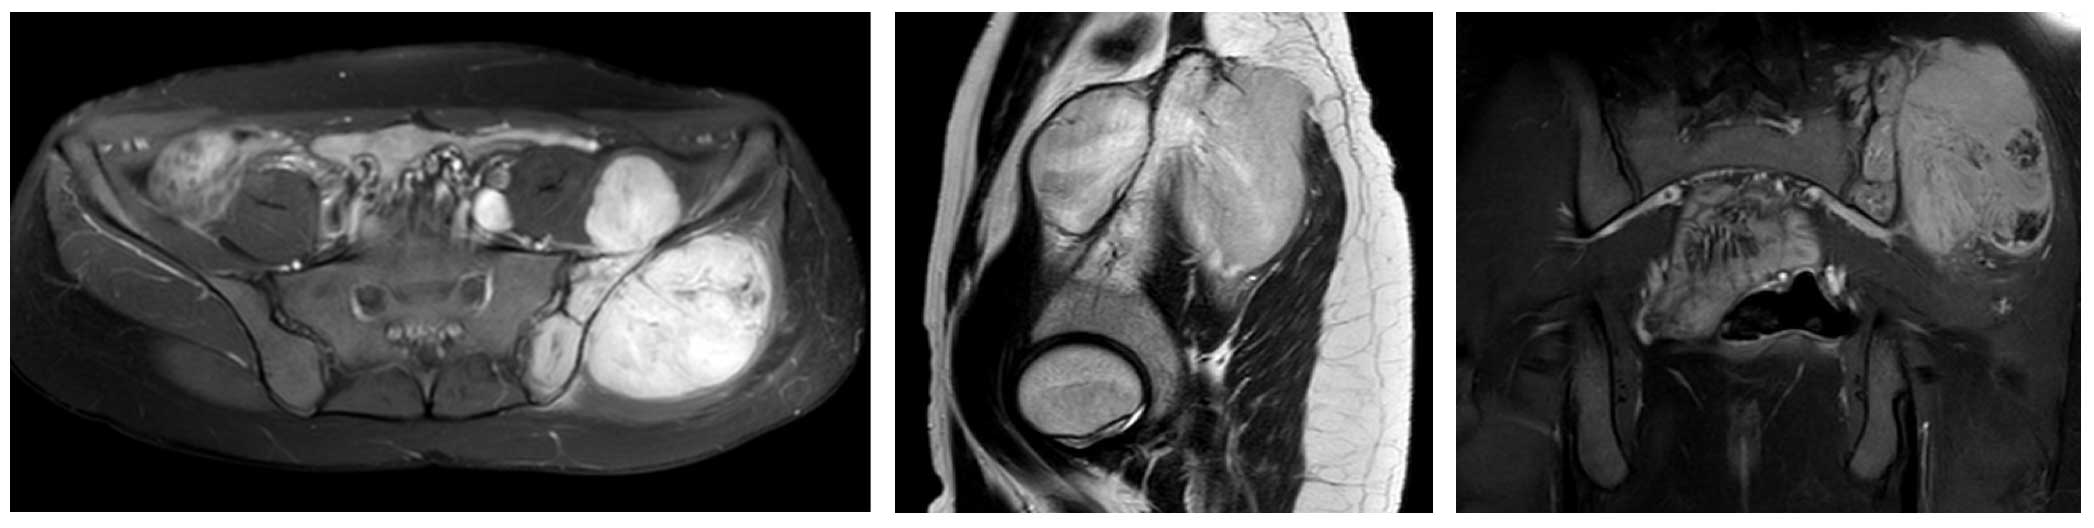

Ameliyat Öncesi: MR’da sol iliak kanat yerleşimli yumuşak dokuya uzanım gösteren büyük boyutlu tümör dokusu görülmekte.